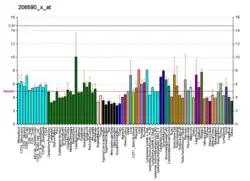

Dopamine receptor D2, also known as D2R, is a protein that, in humans, is encoded by the DRD2 gene. After work from Paul Greengard's lab had suggested that dopamine receptors were the site of action of antipsychotic drugs, several groups, including those of Solomon H. Snyder and Philip Seeman used a radiolabeled antipsychotic drug to identify what is now known as the dopamine D2 receptor.[5] The dopamine D2 receptor is the main receptor for most antipsychotic drugs. The structure of DRD2 in complex with the atypical antipsychotic risperidone has been determined.[6][7]

While optimal dopamine levels favor D1R cognitive stabilization, it is the D2R that mediates the cognitive flexibility in humans.[13][14][15]

Any disordering in equilibration of D2R states, which causes problems in signal transferring between the nervous systems, may lead to diverse serious disorders, such as schizophrenia,[20] autism and Parkinson's disease. In order to assist in the management of these conditions, equilibration between the D2R states is controlled by implementing of agonist and antagonist D2R ligands. In most cases, it was observed that the problems regarding the D2R states may have genetic roots and are controlled by drug therapies. So far, there is no certain treatment for these mental disorders.

Some researchers have previously associated the polymorphism Taq 1A (rs1800497) to the DRD2 gene. However, the polymorphism resides in exon 8 of the ANKK1 gene.[28] DRD2 TaqIA polymorphism has been reported to be associated with an increased risk for developing motor fluctuations but not hallucinations in Parkinson's disease.[29][30] A splice variant in Dopamine receptor D2(rs1076560) was found to be associated with limb truncal tardive dyskinesia and diminished expression factor of Positive and Negative Syndrome Scale (PANSS) in schizophrenia subjects.[31]

Most of the older antipsychotic drugs such as chlorpromazine and haloperidol are antagonists for the dopamine D2 receptor, but are, in general, very unselective, at best selective only for the "D2-like family" receptors and so binding to D2, D3 and D4, and often also to many other receptors such as those for serotonin and histamine, resulting in a range of side-effects and making them poor agents for scientific research. In similar manner, older dopamine agonists used for Parkinson's disease such as bromocriptine and cabergoline are poorly selective for one dopamine receptor over another, and, although most of these agents do act as D2 agonists, they affect other subtypes as well. Several selective D2 ligands are, however, now available, and this number is likely to increase as further research progresses.